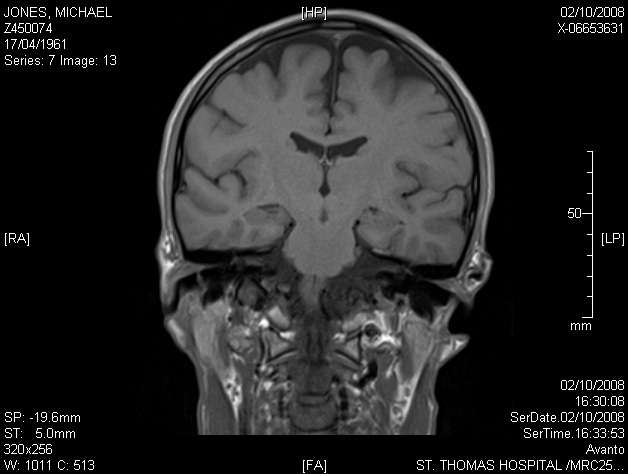

Image 7.13 — vertical (coronal) Brain MRI section at a mid-point between front and rear. There appears to be a small circular object to the left of my spinal column (left & right are reversed in the scan images).

7.13 (detail x4)  |  7.14 (full) »